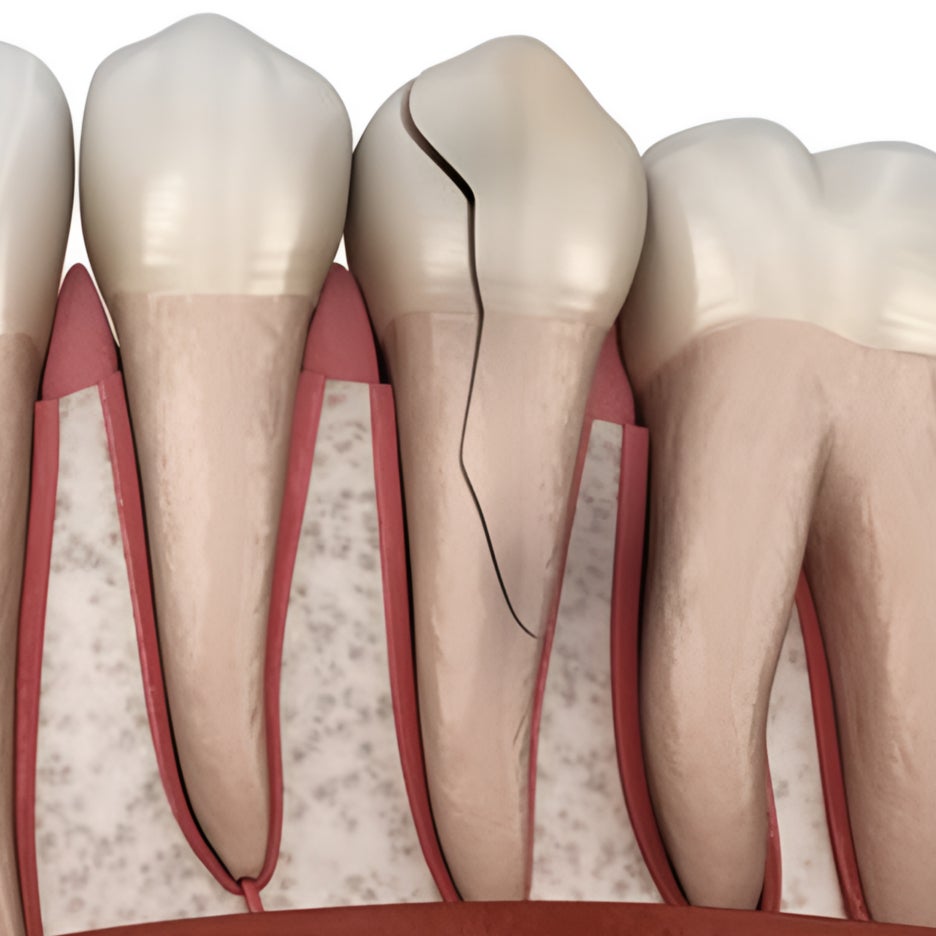

반갑습니다. 치의학 박사 장영준입니다. “이가 너무 아파서 치과에 갔는데 검진 결과 별 이상 없어 보인다고 해서.. 도대체 왜 아픈 걸까요?” 만약 엑스레이와 구강 관찰을